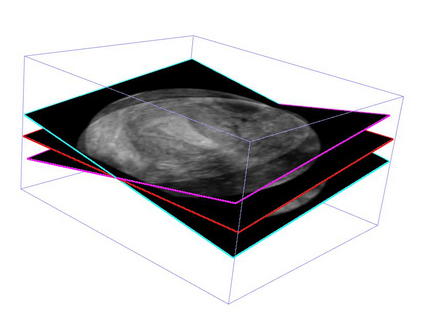

Standard plane (SP) localization is essential in routine clinical ultrasound (US) diagnosis. Compared to 2D US, 3D US can acquire multiple view planes in one scan and provide complete anatomy with the addition of coronal plane. However, manually navigating SPs in 3D US is laborious and biased due to the orientation variability and huge search space. In this study, we introduce a novel reinforcement learning (RL) framework for automatic SP localization in 3D US. Our contribution is three-fold. First, we formulate SP localization in 3D US as a tangent-point-based problem in RL to restructure the action space and significantly reduce the search space. Second, we design an auxiliary task learning strategy to enhance the model's ability to recognize subtle differences crossing Non-SPs and SPs in plane search. Finally, we propose a spatial-anatomical reward to effectively guide learning trajectories by exploiting spatial and anatomical information simultaneously. We explore the efficacy of our approach on localizing four SPs on uterus and fetal brain datasets. The experiments indicate that our approach achieves a high localization accuracy as well as robust performance.

翻译:标准平面( SP) 本地化对于常规临床超声( US) 诊断至关重要 。 与 2D US 相比, 3D US 可以在一次扫描中获得多个查看平面, 并提供完整的剖面, 加上冠冕平面 。 然而, 3D US 人工导航 SP 是困难和偏颇的, 因为方向变化和搜索空间巨大。 在此研究中, 我们引入了一个新的强化学习框架( RL ), 用于3D US 的自动超声波( US) 。 我们的贡献是三维美国 。 首先, 我们将 SP 本地化作为 RL 的正切点问题, 以重组行动空间并显著缩小搜索空间 。 其次, 我们设计了一个辅助任务学习战略, 以增强模型在搜索中识别非 SP 和 SP SP 的微妙差异的能力 。 最后, 我们提出一个空间分析奖赏, 以有效指导在 3D 中利用 空间 和 解剖面信息 学习轨迹 。 我们探索了 4 本地化 4 4 方法的有效性 。